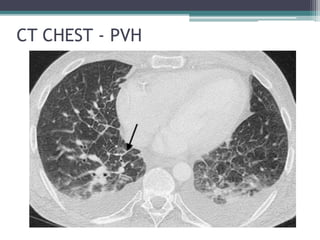

CT CHEST - PVH

• 24.